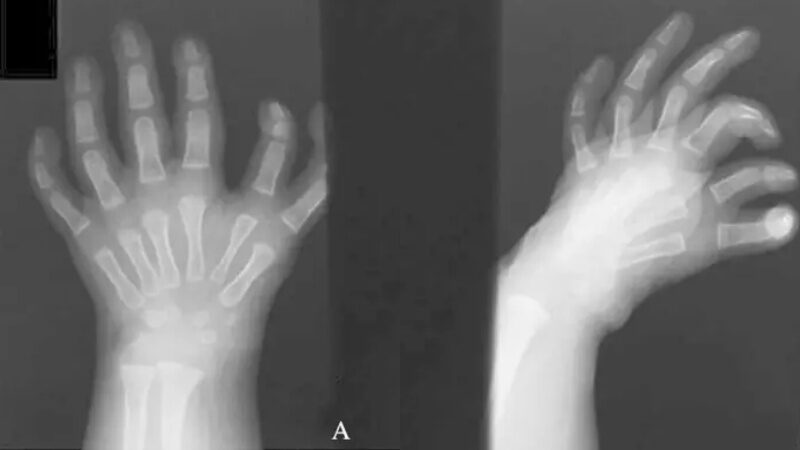

Hội chứng bàn tay gương, còn được gọi là Ulnar Dimelia, là một dị tật bẩm sinh cực kỳ hiếm gặp, ảnh hưởng đến bàn tay.

Nếu con bạn mắc phải tình trạng này, chúng thường sinh ra với 7 - 10 ngón tay trên một hoặc cả hai tay. Điều này có nghĩa là từ điểm giữa của bàn tay, các ngón tay của trẻ trông giống như hình ảnh phản chiếu. Thông thường, không có ngón tay cái.

Thay vào đó, trong hầu hết các trường hợp, trẻ sẽ có ngón giữa. Và ở hai bên, chúng sẽ có sự đối xứng phản chiếu của ba ngón tay - ngón giữa, ngón đeo nhẫn và ngón út.

Khi bạn mắc hội chứng bàn tay gương, thông thường sẽ có hai xương trụ và xương quay bị thiếu. Điều này có xu hướng xảy ra khi chi của bạn vẫn đang trong giai đoạn phát triển như một phôi thai. Xương cổ tay cũng có thể nhân đôi, sau đó làm cho cẳng tay và bàn tay của bạn trông giống như hình ảnh phản chiếu.

Nhìn vào bàn tay, bạn có thể biết con bạn có mắc hội chứng bàn tay gương hay không. Ngoài tình trạng có nhiều ngón tay và không có ngón cái, tình trạng này có thể khiến cổ tay hơi cong. Con bạn có thể thường muốn uốn cong khuỷu tay. Nhưng trong một số trường hợp, khuỷu tay có thể thẳng và khó uốn cong hoặc xoay.